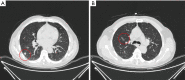

Figure 1

A 75-year-old male smoker with two nodules. (A) A 1.8- cm mGGN in left upper lobe (marked with red circle), was resected by left upper trisegmentectomy; (B) a 1.7- cm mGGN located in the central right upper lobe (marked with red circle), which required lobectomy for resection, was treated by ENB-guided MWA. mGGN, mixed ground glass nodule; ENB, electromagnetic bronchoscopy; MWA, microwave ablation.